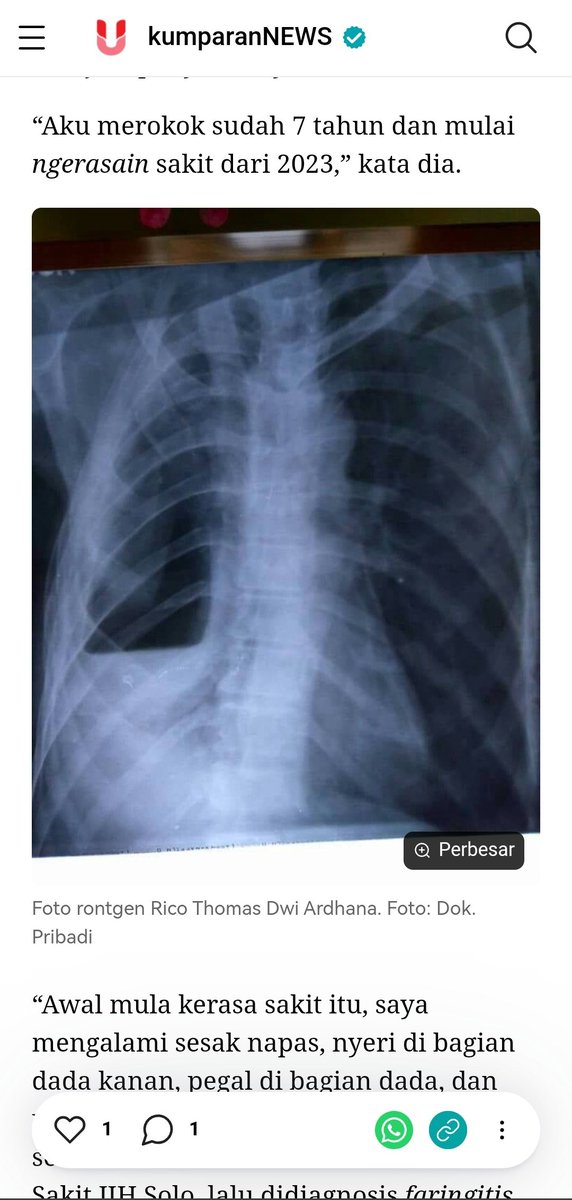

Parunya udah nyerah sebelah sampe hidropneumotoraks begitu, gak cuma sekadar faringitis, bronkitis, GERD. Ini dadanya musti dibolongin dipasang selang. Kena penyakit yg bisa dihindari di usia muda itu musti disyukuri ketauan & bisa diobati, bukan jadi tambah tambeng.

Remaja Klaten Ngerokok Campur Ngevape: Kena Faringitis-Bronkitis Akut, 4 Kali Masuk RS #newsupdate #update #news #text kumparan.com/kumparannews/r…